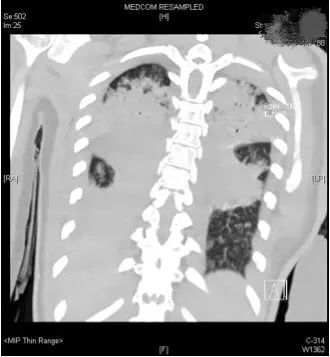

評估結(jié)果不容樂觀,呼吸機的支持水平要求很高,100%純氧條件下小文體內(nèi)的氧分壓才勉強達標,持續(xù)高燒超過40攝氏度,CT復查提示兩肺幾乎全部實變,炎癥指標非常高。

(小文的影像檢查顯示,雙肺幾乎完全實變)